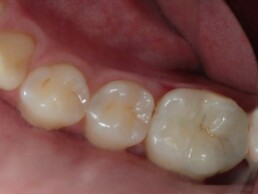

Dans les années 90 le premier matériau bio régénérateur à usage clinique à été l’Agrégat de trioxyde minéral(MTA)

C était le précurseur des produits actuels ,ces produits ont évolués vers le silicate de calcium (commercialisé sous le nom de « Biodentine »). Ce matériau est plus résistant et il ne colore pas la dent.

Ce procédé stimule le dépôt d’hydroxyapatite, il ne présente aucune toxicité et il va créer un joint hermétique pour protéger le nerf et la pulpe dentaire, il y a stimulation des odontoblastes (cellules conjonctives de construction du tissu dentaire) en résumé les silicates de calcium ont le pouvoir de cicatriser le tissu pulpaire et d’éviter la dévitalisation.